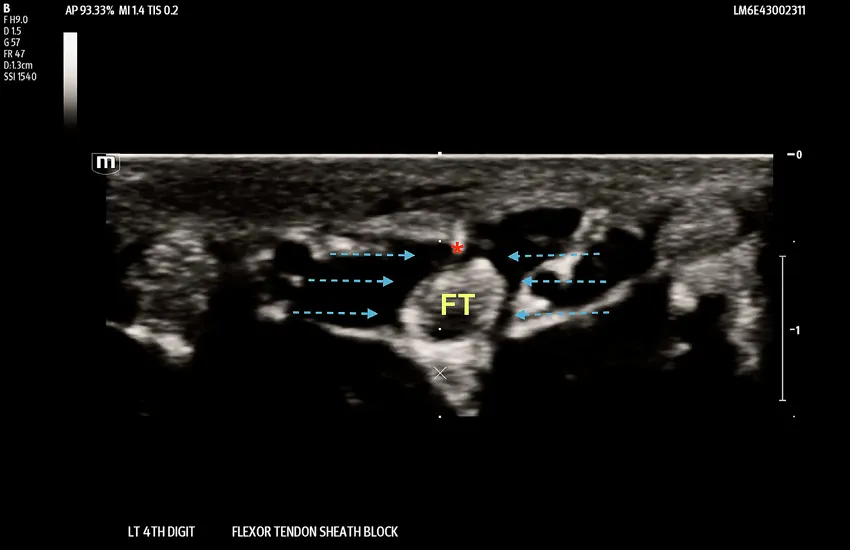

Fig. 2. Out-of-plane needle technique showing the tip of a 27-gauge needle in the flexor tendon sheath space (red asterisk) and “horseshoe” distribution of anesthetic around the flexor tendon (dashed blue arrows). FT- Flexor Tendon (yellow). (For interpretation of the references to colour in this figure legend, the reader is referred to the web version of this article.)